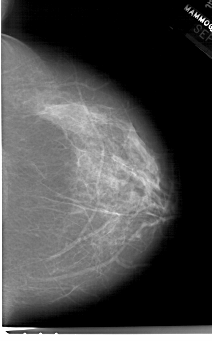

A_1514_1.RIGHT_MLO

RIGHT_MLO LINES 6421 PIXELS_PER_LINE 4111 BITS_PER_PIXEL 12 RESOLUTION 43.5 NON_OVERLAY